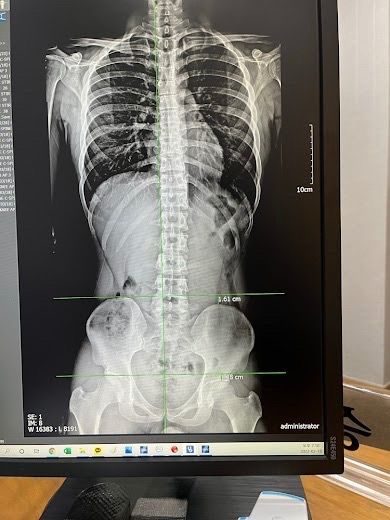

골반 틀어짐이 0.5cm 이내 이면 정상범위로 볼 수 있지만 1cm 이상이면 신체 불균형과 통증이 유발될 수가 있으며 자세 교정을 위한 재활치료가 필요하다고 볼 수 있습니다.

사진만으로 정확한 각도측정이 어렵지만, 척추와 골반라인이 약간 좌우 차이가있어 가벼운 비대칭은 의심됩니다. 다만 심한상태라고 단정하기는 어렵습니다. 말씀하신 햄스트링/종아리 저림은 골반불균형+허리신경자극이 함께 있을 가능성이 있습니다. 특히 안전화처럼 딱딱하고 무거운신발은 하체충격을 늘려 증상을 악화시킬수 있습니다.단순골반 틀어짐보다 자세,근육불균형, 허리상태를 같이보는것이 중요합니다. 스트레칭과 코어운동으로 균형을 맞추는것이 도움이됩니다. 답변이 도움되셨길 바랍니다!

1. 엑스레이 상에서는 1.6cm정도 차이가 방샐할 수 있지만, 정적인 상태에서 발생하는 차이가 반드시 문제가 되는 것은 아닙니다.

공유해주신 엑스레이상 오른쪽 골반이 약간 올라가고 왼쪽골반이 낮은 것으로 보이며 엑스레이상 차이는 약간 있지만 엑스레이 같은 경우 찍는 방향 및 자세에 따라 약간의 차이가 있을 수 있기에 조금 더 정확한 것은 직접 만져보고 테스트를 해보는게 조금 더 좋을 것으로 생각되며 일단 공유해주신 사진상으로는 골반의 불균형이 없다고 보기는 어려우며 약간의 불균형은 있는 상태로 보입니다.